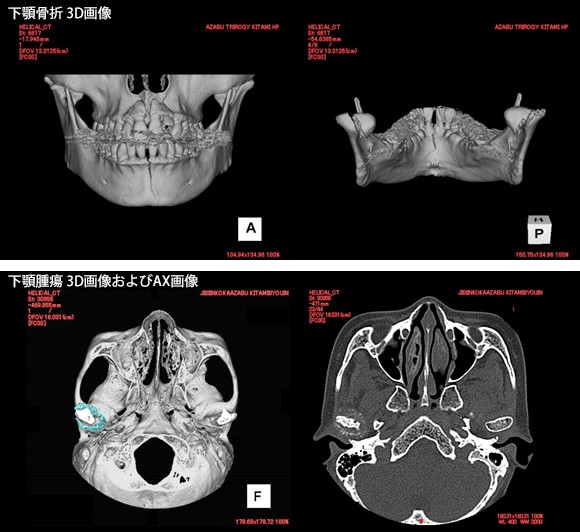

耳小骨や腫瘍等の、より高精細な3次元画像を提供しています。

3次元画像(3D)

パノラマ撮影は、湾曲した顎骨を展開した画像として撮影し、親知らずの抜歯の際、下歯槽神経管の位置を知るため重要な撮影です。また腫瘍病変では、位置や広がりを容易にとらえることができます。セファロX線撮影では、下顎骨の左右非対称、上顎骨と下顎骨の相互的位置関係等を評価します。